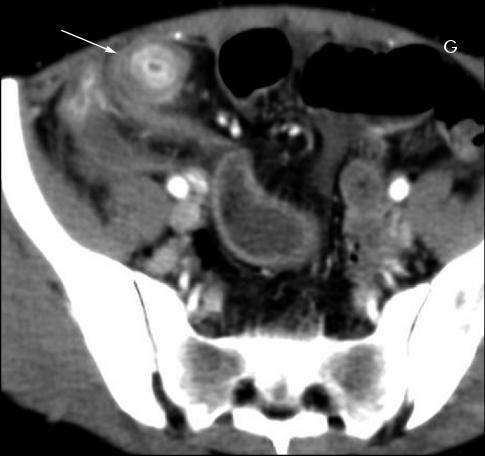

Maladie de Crohn du rectum .

Image epassisement du rectum avec infiltration de la

graisse entre la couche sousmuqueuse et la

couche muscculaire . Ce qui forme en

signe de halo " fat halo sign " |

|

Image

radiologique IRM est l'epaissisement parietale

et cette technique c'est le bien pour localisatrice de

lesion . La T2 avec TE court peut

caracterise de l'epaissisement de paroi de l'intestin , de

la differenciation

complex muco-sous muqueux et recherche de oedeme sous muqueuse

. La T1 fatsat peut utilise pour recherche des fistules ,des lesions inflamatoires , lesions fibreuses et des pseudo-polyp

.

Image IRM en coupe axiale T1

fat sat du maladie de Crohn . Epaissisement de la

paroi du colon avec infiltration graisseuse

extramurale du colon . |

Lesion epaissisement de

l'intestin , aspect hypervascularisation en peigne

et fistule entero-vesicale . Infection urinaire

recidivante avec epaissisement de la paroi du vessie

. Image IRM en coupe sagitale . |